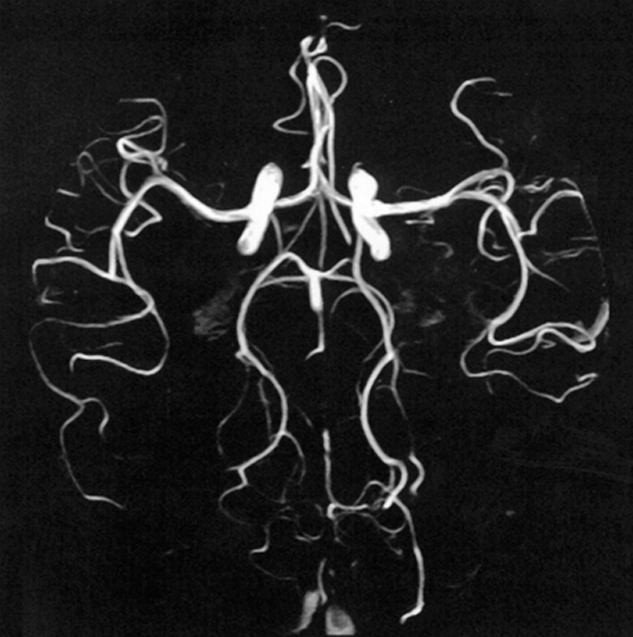

Figure 14-12:

Time-of-flight angiography.